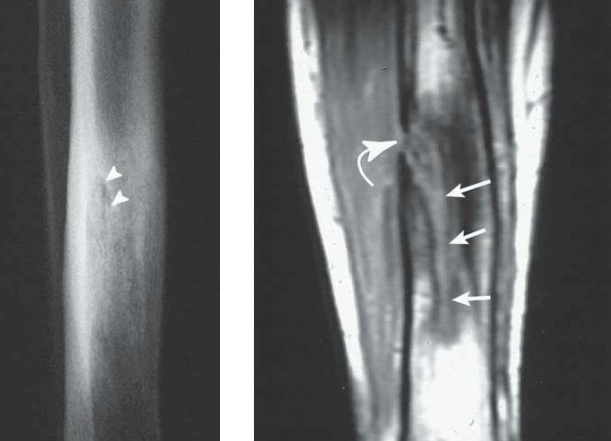

- Zones de lyse et de sclérose

- Sinus de drainage ou Séquestre Osseux

- Cloaque = Communication entre la moelle et les tissus mous

Sinus de drainage